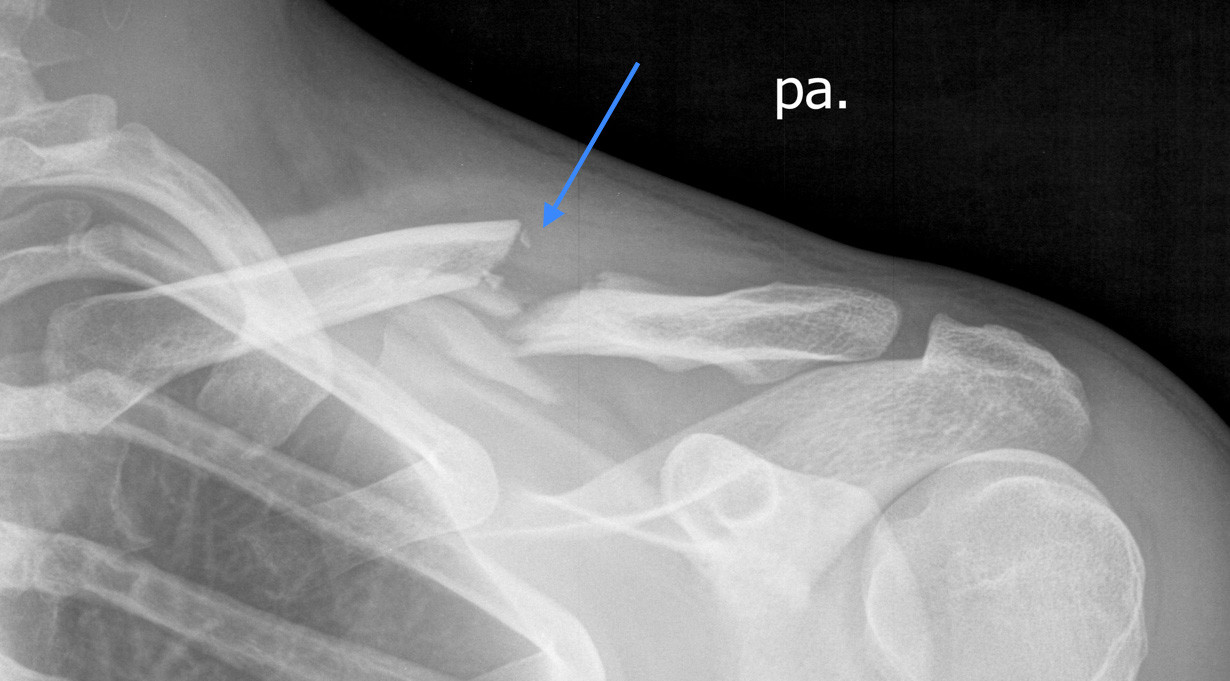

Verschobener Bruch des Schlüsselbeins

Abb. 1: Verschobener Bruch des Schlüsselbeins (Pfeil zeigt auf den Bruchspalt)